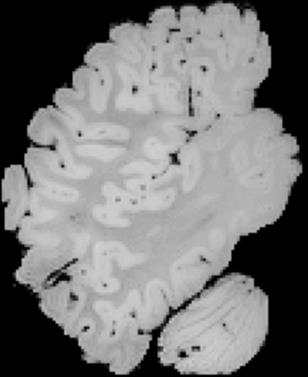

In neuroimaging, MRI tissue properties characterize underlying neurobiology, provide quantitative biomarkers for neurological disease detection and analysis, and can be used to synthesize arbitrary MRI contrasts. Estimating tissue properties from a single scan session using a protocol available on all clinical scanners promises to reduce scan time and cost, enable quantitative analysis in routine clinical scans and provide scan-independent biomarkers of disease. However, existing tissue properties estimation methods - most often $\mathbf{T_1}$ relaxation, $\mathbf{T_2^*}$ relaxation, and proton density ($\mathbf{PD}$) - require data from multiple scan sessions and cannot estimate all properties from a single clinically available MRI protocol such as the multiecho MRI scan. In addition, the widespread use of non-standard acquisition parameters across clinical imaging sites require estimation methods that can generalize across varying scanner parameters. However, existing learning methods are acquisition protocol specific and cannot estimate from heterogenous clinical data from different imaging sites. In this work we propose an unsupervised deep-learning strategy that employs MRI physics to estimate all three tissue properties from a single multiecho MRI scan session, and generalizes across varying acquisition parameters. The proposed strategy optimizes accurate synthesis of new MRI contrasts from estimated latent tissue properties, enabling unsupervised training, we also employ random acquisition parameters during training to achieve acquisition generalization. We provide the first demonstration of estimating all tissue properties from a single multiecho scan session. We demonstrate improved accuracy and generalizability for tissue property estimation and MRI synthesis.